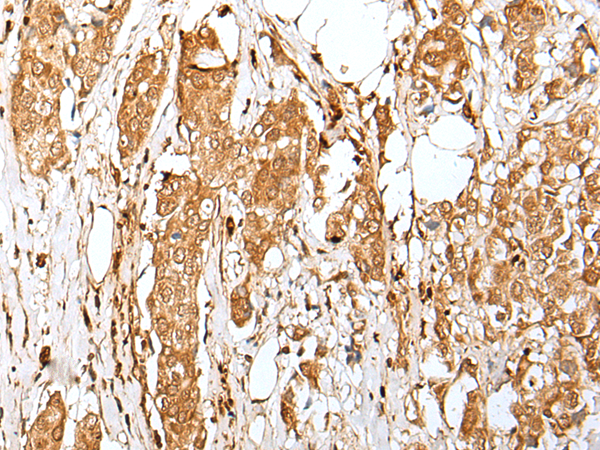

IHC positive control: |

Human tonsil and human breast cancer |

IHC Recommend dilution: |

30-150 |